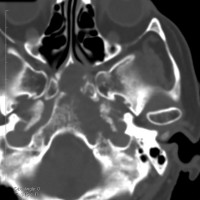

骨軟骨腫が若い時からあって壮年になってから悪性化した軟骨肉腫です。20代のときに右外転神経麻痺が生じて20年以上そのまま経過しました。左のCTでは頭蓋骨の真ん中の斜台というところに異常な骨があって,良性の骨軟骨腫のように見えます。でも右側のMRIでは脳幹部に深く食い込む柔らかい腫瘍の部分が写っていてこれは軟骨肉腫を疑う像です。手術摘出と術後の放射線治療をしました。